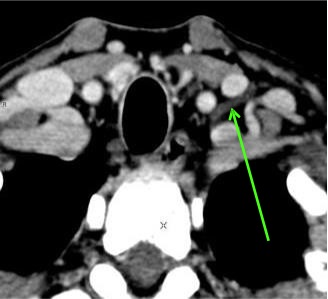

乳糜池 Cisterna Chyli

胸导管弓

Arch of TD visible in 57%

CT after lymphography